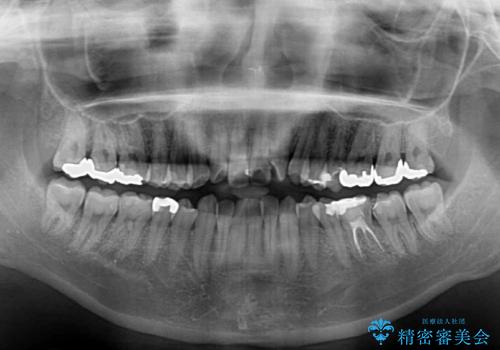

- 前歯の捻れを気にして来院された患者様です。

上顎前歯が捻れて前方に飛び出しており、下顎前歯もそれに沿うようにデコボコとなっていました。

IPR(歯と歯の間を削る処置)によりスペースを獲得して上下前歯のデコボコを改善し、インビザラインにて矯正治療を行うこととしました。